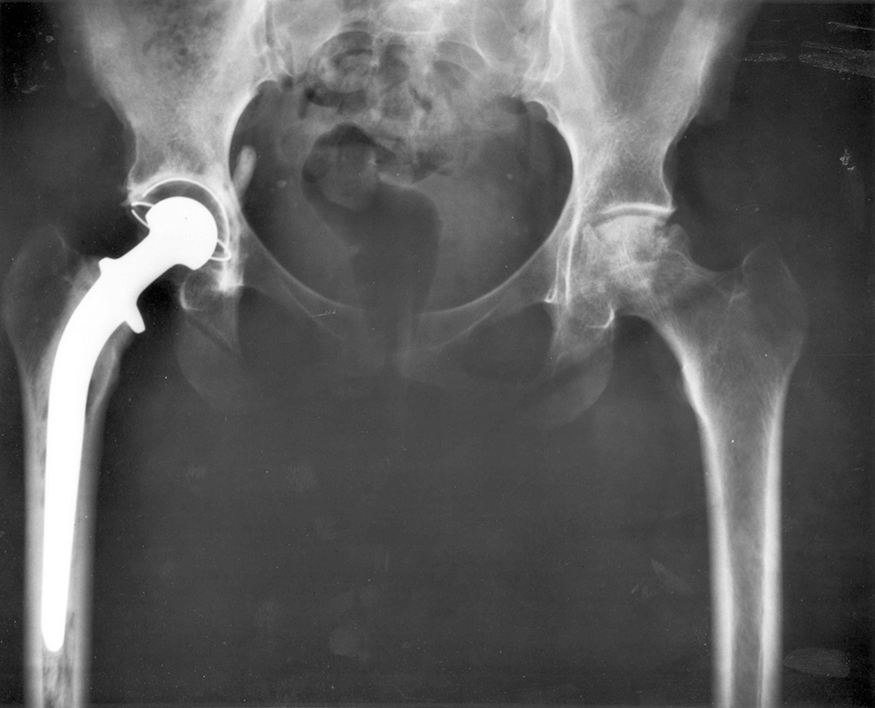

Figure 5.1 Total hip replacement surgery has become a common procedure. The head (or ball) of the patient’s femur fits into a cup that has a hard plastic-like inner lining.

(credit: National Institutes of Health, via Wikimedia Commons)

Describe the forces on the hip joint. What means are taken to ensure that this will be a good movable joint? From the photograph (for an adult) in

Figure 5.1, estimate the dimensions of the artificial device.

Many people have experienced the slipperiness of walking on ice. However, many parts of the body, especially the joints, have much smaller

coefficients of friction—often three or four times less than ice. A joint is formed by the ends of two bones, which are connected by thick tissues. The

knee joint is formed by the lower leg bone (the tibia) and the thighbone (the femur). The hip is a ball (at the end of the femur) and socket (part of the

pelvis) joint. The ends of the bones in the joint are covered by cartilage, which provides a smooth, almost glassy surface. The joints also produce a

fluid (synovial fluid) that reduces friction and wear. A damaged or arthritic joint can be replaced by an artificial joint (Figure 5.3). These replacements can be made of metals (stainless steel or titanium) or plastic (polyethylene), also with very small coefficients of friction.

Figure 5.3 Artificial knee replacement is a procedure that has been performed for more than 20 years. In this figure, we see the post-op x rays of the right knee joint

replacement. (credit: Mike Baird, Flickr)